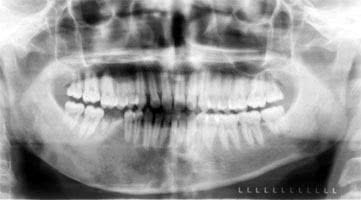

La Parodontologia è un ramo dell’Odontoiatria, che si occupa dello studio delle malattie che riguardano la bocca ed in modo particolare dei denti. Il parodonto è costituito da : gengiva; osso alveolare; cemento radicolare...